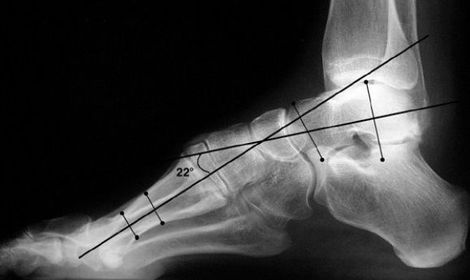

| What is this angle called? What is normal? What does an increased angle indicate? | Talo-calcaneal angle. 25-45 degrees. Increased angle = hindfoot valgus |